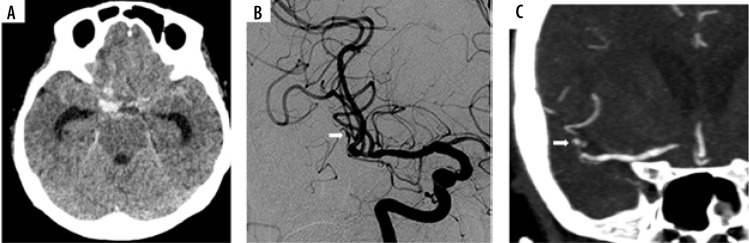

Results: Forty-seven patients were included in our study, with a median age of 55 years and a range of 28-81 years. Thirty-seven had diffuse SAH (66%), and 16 had perimesencephalic SAH (34%). The repeat CTA revealed 2 causa-tive vascular lesions (a right PICA aneurysm and a mycotic aneurysm) in 2 separate patients (yield of 4.3%), both of whom had diffuse SAH (yield of 6.5%). In retrospect, none of these vascular lesions were evident in the initial CTA and DSA. No evidence of re-bleeding was observed in the follow-up period.